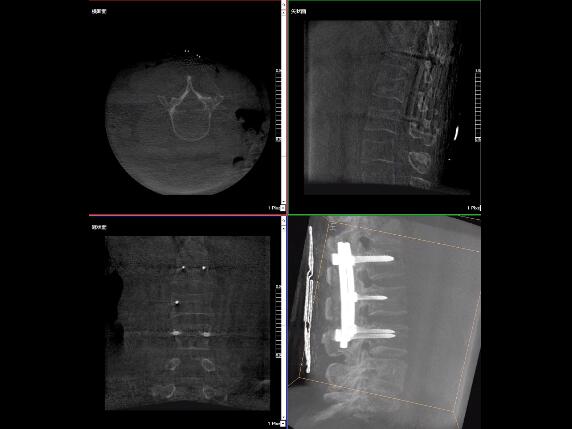

比如,醫(yī)生在做PKP(椎體成形術(shù))的時(shí)候,或者在置入螺釘?shù)臅r(shí)候,醫(yī)生需要在影像上看到螺釘打進(jìn)去的進(jìn)針點(diǎn)以及進(jìn)針的路徑。比如,我們在打腰椎的釘子時(shí)需要看到“貓眼”。我們只有把釘子完全打在“貓眼”里面,才能確保釘子打在了椎弓根里,所以對(duì)“貓眼”的顯影就非常重要。

最后我要強(qiáng)調(diào)一點(diǎn),以上我提到的“貓眼”,在二維的X光片上,醫(yī)生是靠經(jīng)驗(yàn)去判斷釘子是否打在椎弓根里,這個(gè)時(shí)候如果我們的設(shè)備再先進(jìn)一點(diǎn),診斷手段再多一點(diǎn),如果我們能夠把二維的影像轉(zhuǎn)換為三維的影像,可能就不會(huì)完全依賴醫(yī)生的經(jīng)驗(yàn)。

我們可以在三維的圖像中直觀的看到釘子到底在不在椎弓根里面,這樣可以指導(dǎo)我們準(zhǔn)確的進(jìn)針,指導(dǎo)我們進(jìn)行一場高質(zhì)量的手術(shù),可以起到事半功倍的效果,手術(shù)會(huì)簡單得多,病人的預(yù)后也會(huì)好得多。